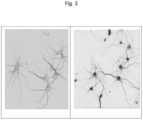

FIG.3 is a black and white, image reversed photograph of neurons that have been exposed to Lipid Mix A LNP containing GFP mRNA (left panel), and Lipid Mix G formulated nanoparticles containing GFP mRNA (right panel). In both panels, MAP2 antibody staining (a neuronal marker) shows the outline of the neurons, DAPI stain shows the nuclei, and GFP expression in the neurons is shown as darkest staining. Merged images showing DAPI, MAP2, and GFP staining, establish GFP expression in the live neurons treated with Lipid Mix G LNP;

Fluorescence microscopy or confocal microscopy was used to identify GFP protein levels.FIG.3 is a black and white, image reversed photograph of confocal microscopy of live neurons that have been treated with labeled Lipid Mix G LNP containing GFP. The reverse image showed the results better than the original colour photograph for black and white image. Both images include DAPI, a nuclear stain. The rightmost image shows MAP2 (a neuronal marker) antibody staining, and the leftmost image is a merge showing DiD, MAP2, and GFP in one image. In both panels, MAP2 antibody staining (a neuronal marker) shows the outline of the neurons. DAPI staining of the successfully delivered mRNA to the nuclei is dark in both the left and the right panel. GFP expression in the neurons is shown as even darker staining predominantly in the right panel. Not shown, no GFP expression was seen in neurons treated with Lipid Mix A mRNA LNP by the same confocal imaging process.

Lipid Mix G LNP was an effective mRNA delivery vehicle in live neurons.